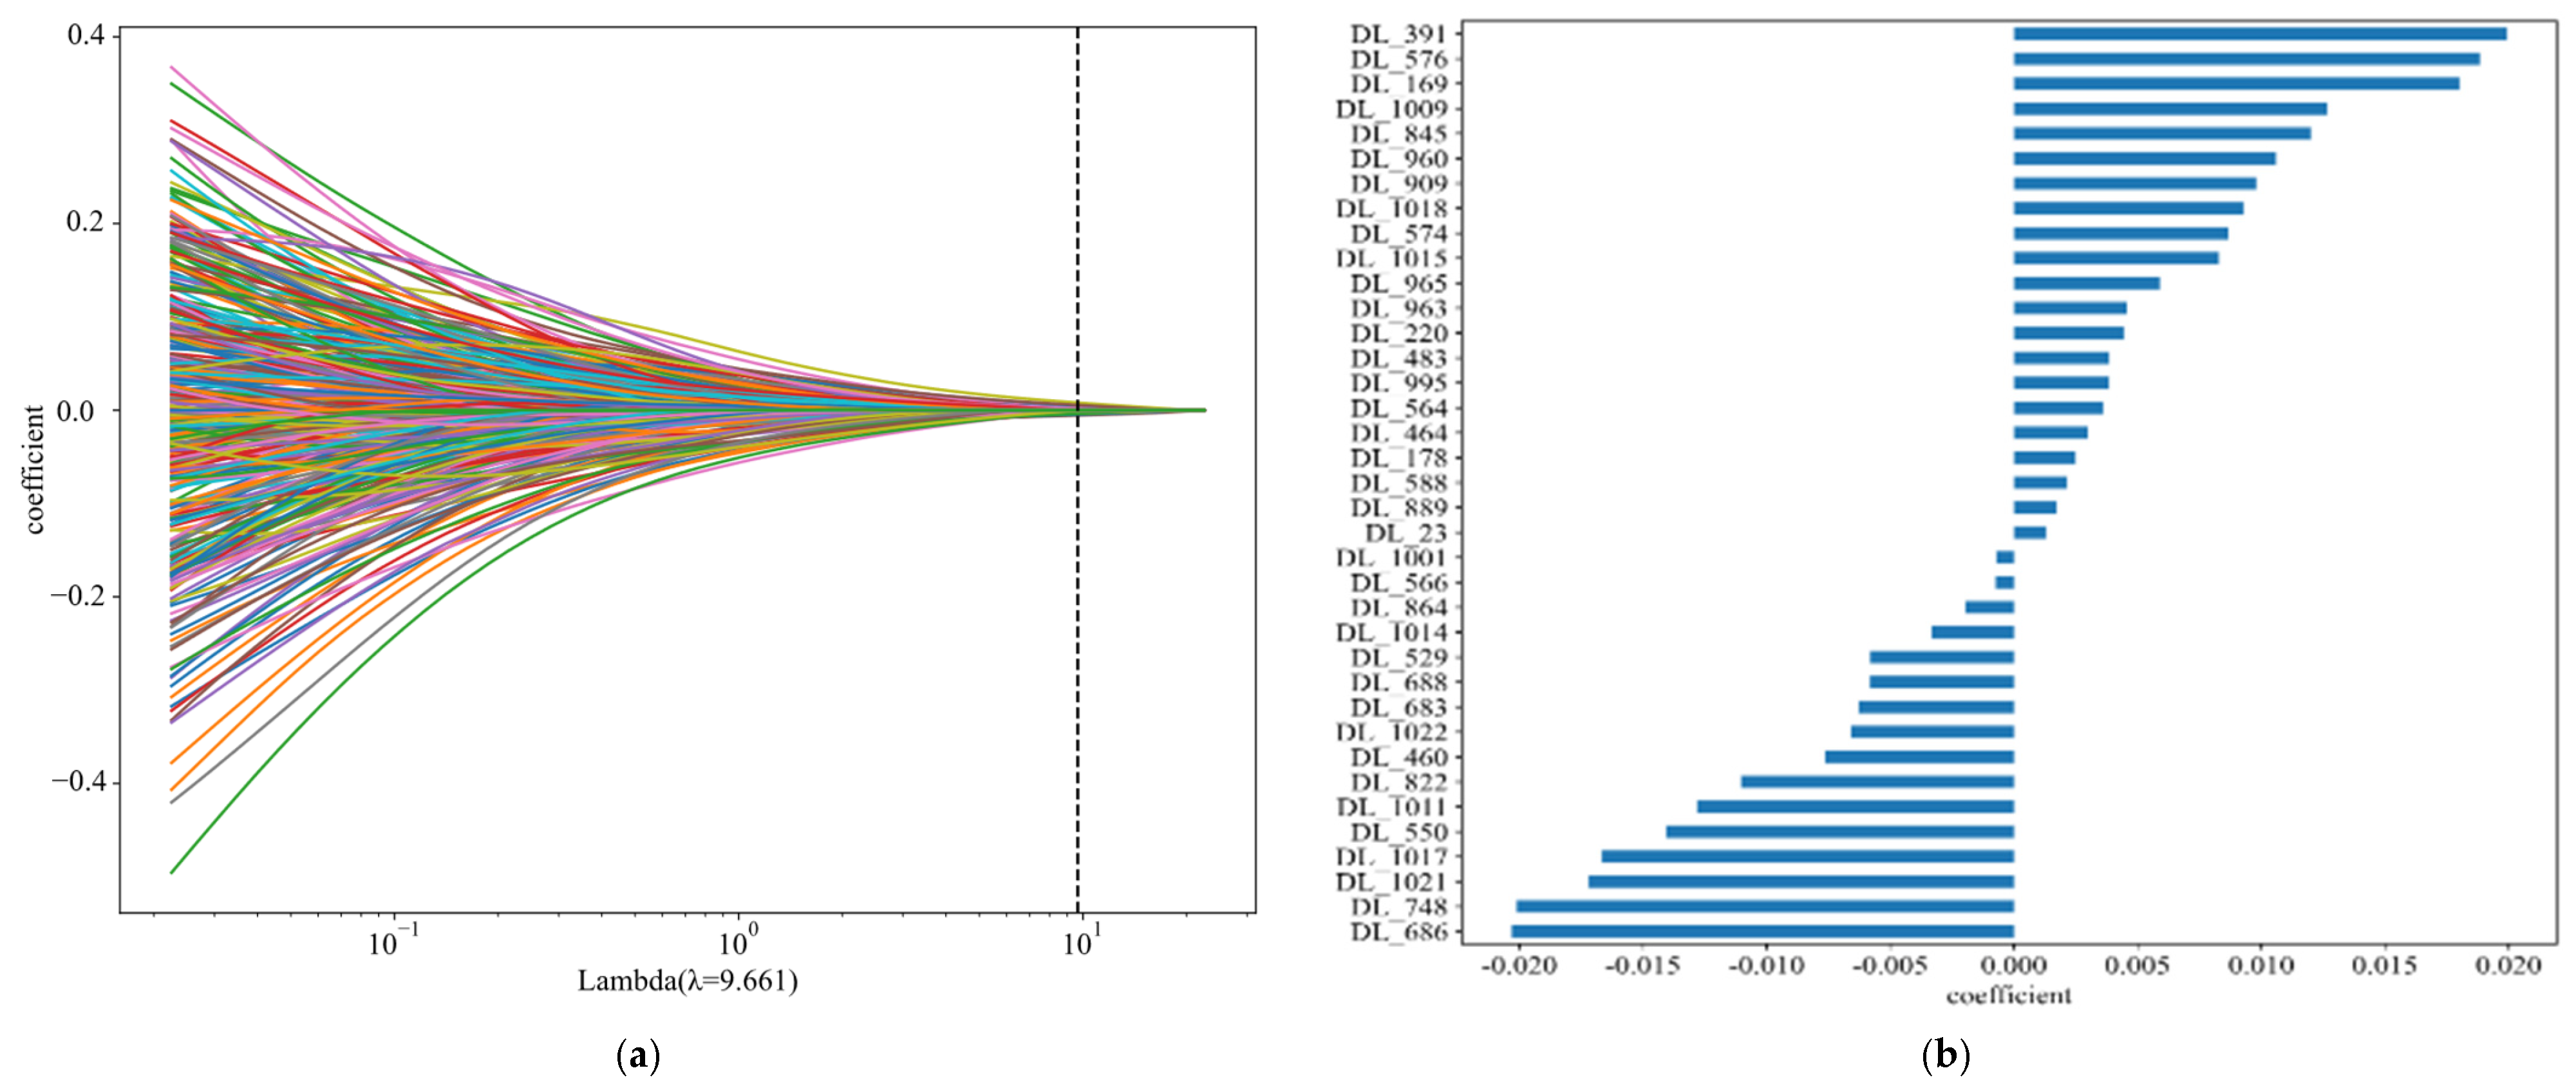

5.2. Survival Time Prediction